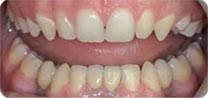

安卓健临床案例分享

单颗 多颗牙缺失、半全口牙缺失 ,假牙不适者